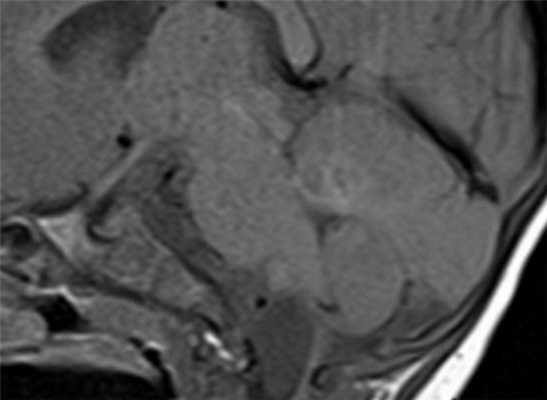

Результаты. Из 50 пациентов у 12 человек (24%) опухоль располагалась в области языка, у 15 пациентов (30%) в области дна полости рта, на миндалинах у 16 человек (32%), мягком небе - 5 человек (10%), слизистая щеки - 1 пациент (2%), альвеолярный отросток - 1человек (2%). По распространенности опухолевого процесса 29 пациентов были с Т3 стадией (58%), 7 пациентов с Т4 (14%), 12 пациентов с Т2 (24%), 2-с Т1(4%). По степени поражения лимфатических узлов 14 человек с N1(28%) стадией, 10 - с N2(20%), у 2 человек - N3 стадия (5%). В 2 случаях (4%) было выявлено поражение нижней челюсти.

Анализ результатов МСКТ и МРТ у больных с установленным диагнозом рака орофарингеальной зоны включал оценку размеров опухоли, распространенности опухолевого процесса по мышцам и костным структурам, переход за среднюю линию, степень инфильтрации межмышечной и подкожной клетчатки, поражение лимфатических узлов. Было установлено, что МСКТ - семиотика плоскоклеточного рака полости рта и ротоглотки соответствует МРТ-семиотике и включает в себя прямые и косвенные признаки. Прямыми признаками злокачественной опухоли являлись объемное разрастание патологической ткани, истончение жирового слоя или полная облитерация жировых пространств, инфильтрация мышечной ткани и костная деструкция. Косвенными признаками были структурная неоднородность ткани (при наличии некроза), изменение показателей плотности после введения контрастного вещества при МСКТ - исследовании и изменение сигнала при МРТ.

С помощью КТ сложно было выявлять опухоли малых размеров (Т1стадия) и их границы в результате низкой контрастности, а также новообразования с поверхностным распространением (рис. 1). Вместе с тем, 72,0% обследованных больных имели Т3, Т4 стадии опухолевого процесса и после болюсного введения контрастного вещества контрастность опухоли повышалась. С увеличением размера опухоли отмечалась неоднородность усиления из-за наличия некроза (рис. 2). Жировые пространства подъязычной области в нормальном состоянии представляют собой симметричную зону низкой плотности между челюстно-подъязычной и подбородочно-подъязычной мышцами. Облитерация жировых пространств подъязычной области служила основным показателем опухолевого поражения при выявлении небольших образований дна полости рта (рис. 3,4).

Особенностью МРТ являлась высокая контрастность мягких тканей. Плотные костные ткани или зубоврачебный материал не создавали артефактов, что давало возможность получать четкое изображение опухоли полости рта, определять распространение в мягкие ткани, глубокие отделы орофарингеальной зоны, в область неба. На Т1-ВИ все опухоли имели ту же интенсивность сигнала, как у окружающих мышц или слабее (рис.7).

После введения контрастного вещества все опухоли показывали усиление сигнала. При локализации опухолевого процесса в области языка (12 пациентов) границы опухоли визуализировались более четко. В режиме Т2-ВИ опухолевые узлы проявлялись более высокой интенсивностью сигнала, чем у окружающих мышц (рис. 8).

Сложно было с помощью МРТ визуализировать опухоли любых размеров с поверхностным распространением, не выходящие за пределы слизистой оболочки. Опухоли малых размеров (Т1 стадия) в 2 наблюдениях были однородны, не имели центральной зоны некроза и сливались с мышцами. С увеличением размера опухолевого узла отмечалась неоднородность структуры. В наших исследованиях удалось выявить небольшие опухоли Т1 и Т2 стадий, локализованные в области языка и дна полости рта. В 9 наблюдениях опухоли Т2 стадии, не накапливающие контраст при МСКТ исследовании, хорошо визуализировались при МРТ в режимах Т2-ВИ, STIR, проявляясь сигналом высокой интенсивности. Можно было четко видеть границы опухоли и оценить ее размеры (рис. 9,10).

Не возникало сложностей в выявлении опухолевых узлов Т3, Т4 стадий, имевших все отмеченные выше признаки в различных сочетаниях в 36 исследованиях (рис. 11). Из 50 обследованных с помощью МСКТ и МРТ пациентов у 26 (52,0%) были выявлены метастазы в лимфатических узлах шеи. Поражались преимущественно лимфатические узлы I-II уровня. Признаками метастаза плоскоклеточного рака в лимфатических узлах были: увеличение размера лимфатического узла более 1,0 см, изменение формы лимфатического узла с бобовидной на округлую, структурные нарушения в узле, нечеткость наружных контуров узла, уплотнение окружающей жировой ткани на КТ или изменение сигнала на МРТ.